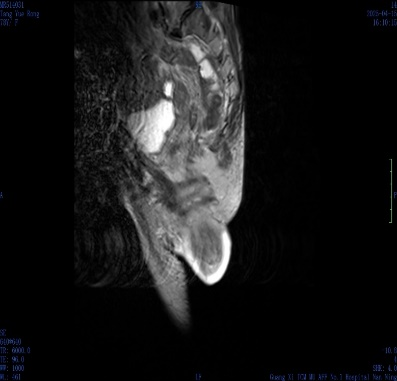

肛肠外科检查发现,周奶奶的肛门处有约 8 cm 脱出肿物,呈「宝塔状」,肛门括约肌明显松弛。结合排粪造影及 MRI 提示,诊断为 III 度直肠脱垂。